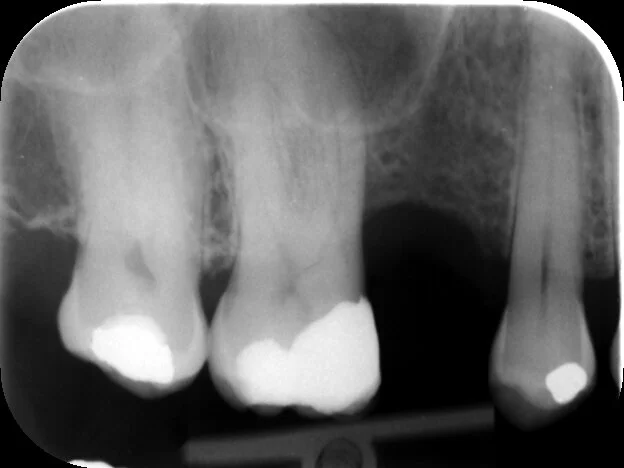

Non-Surgical Root Canal Treatment UR6

The UR6 was causing some pain, the vitality test result was negative, we decided to perform root canal treatment.

The angle of this PA hid the true nature of the canal curvature